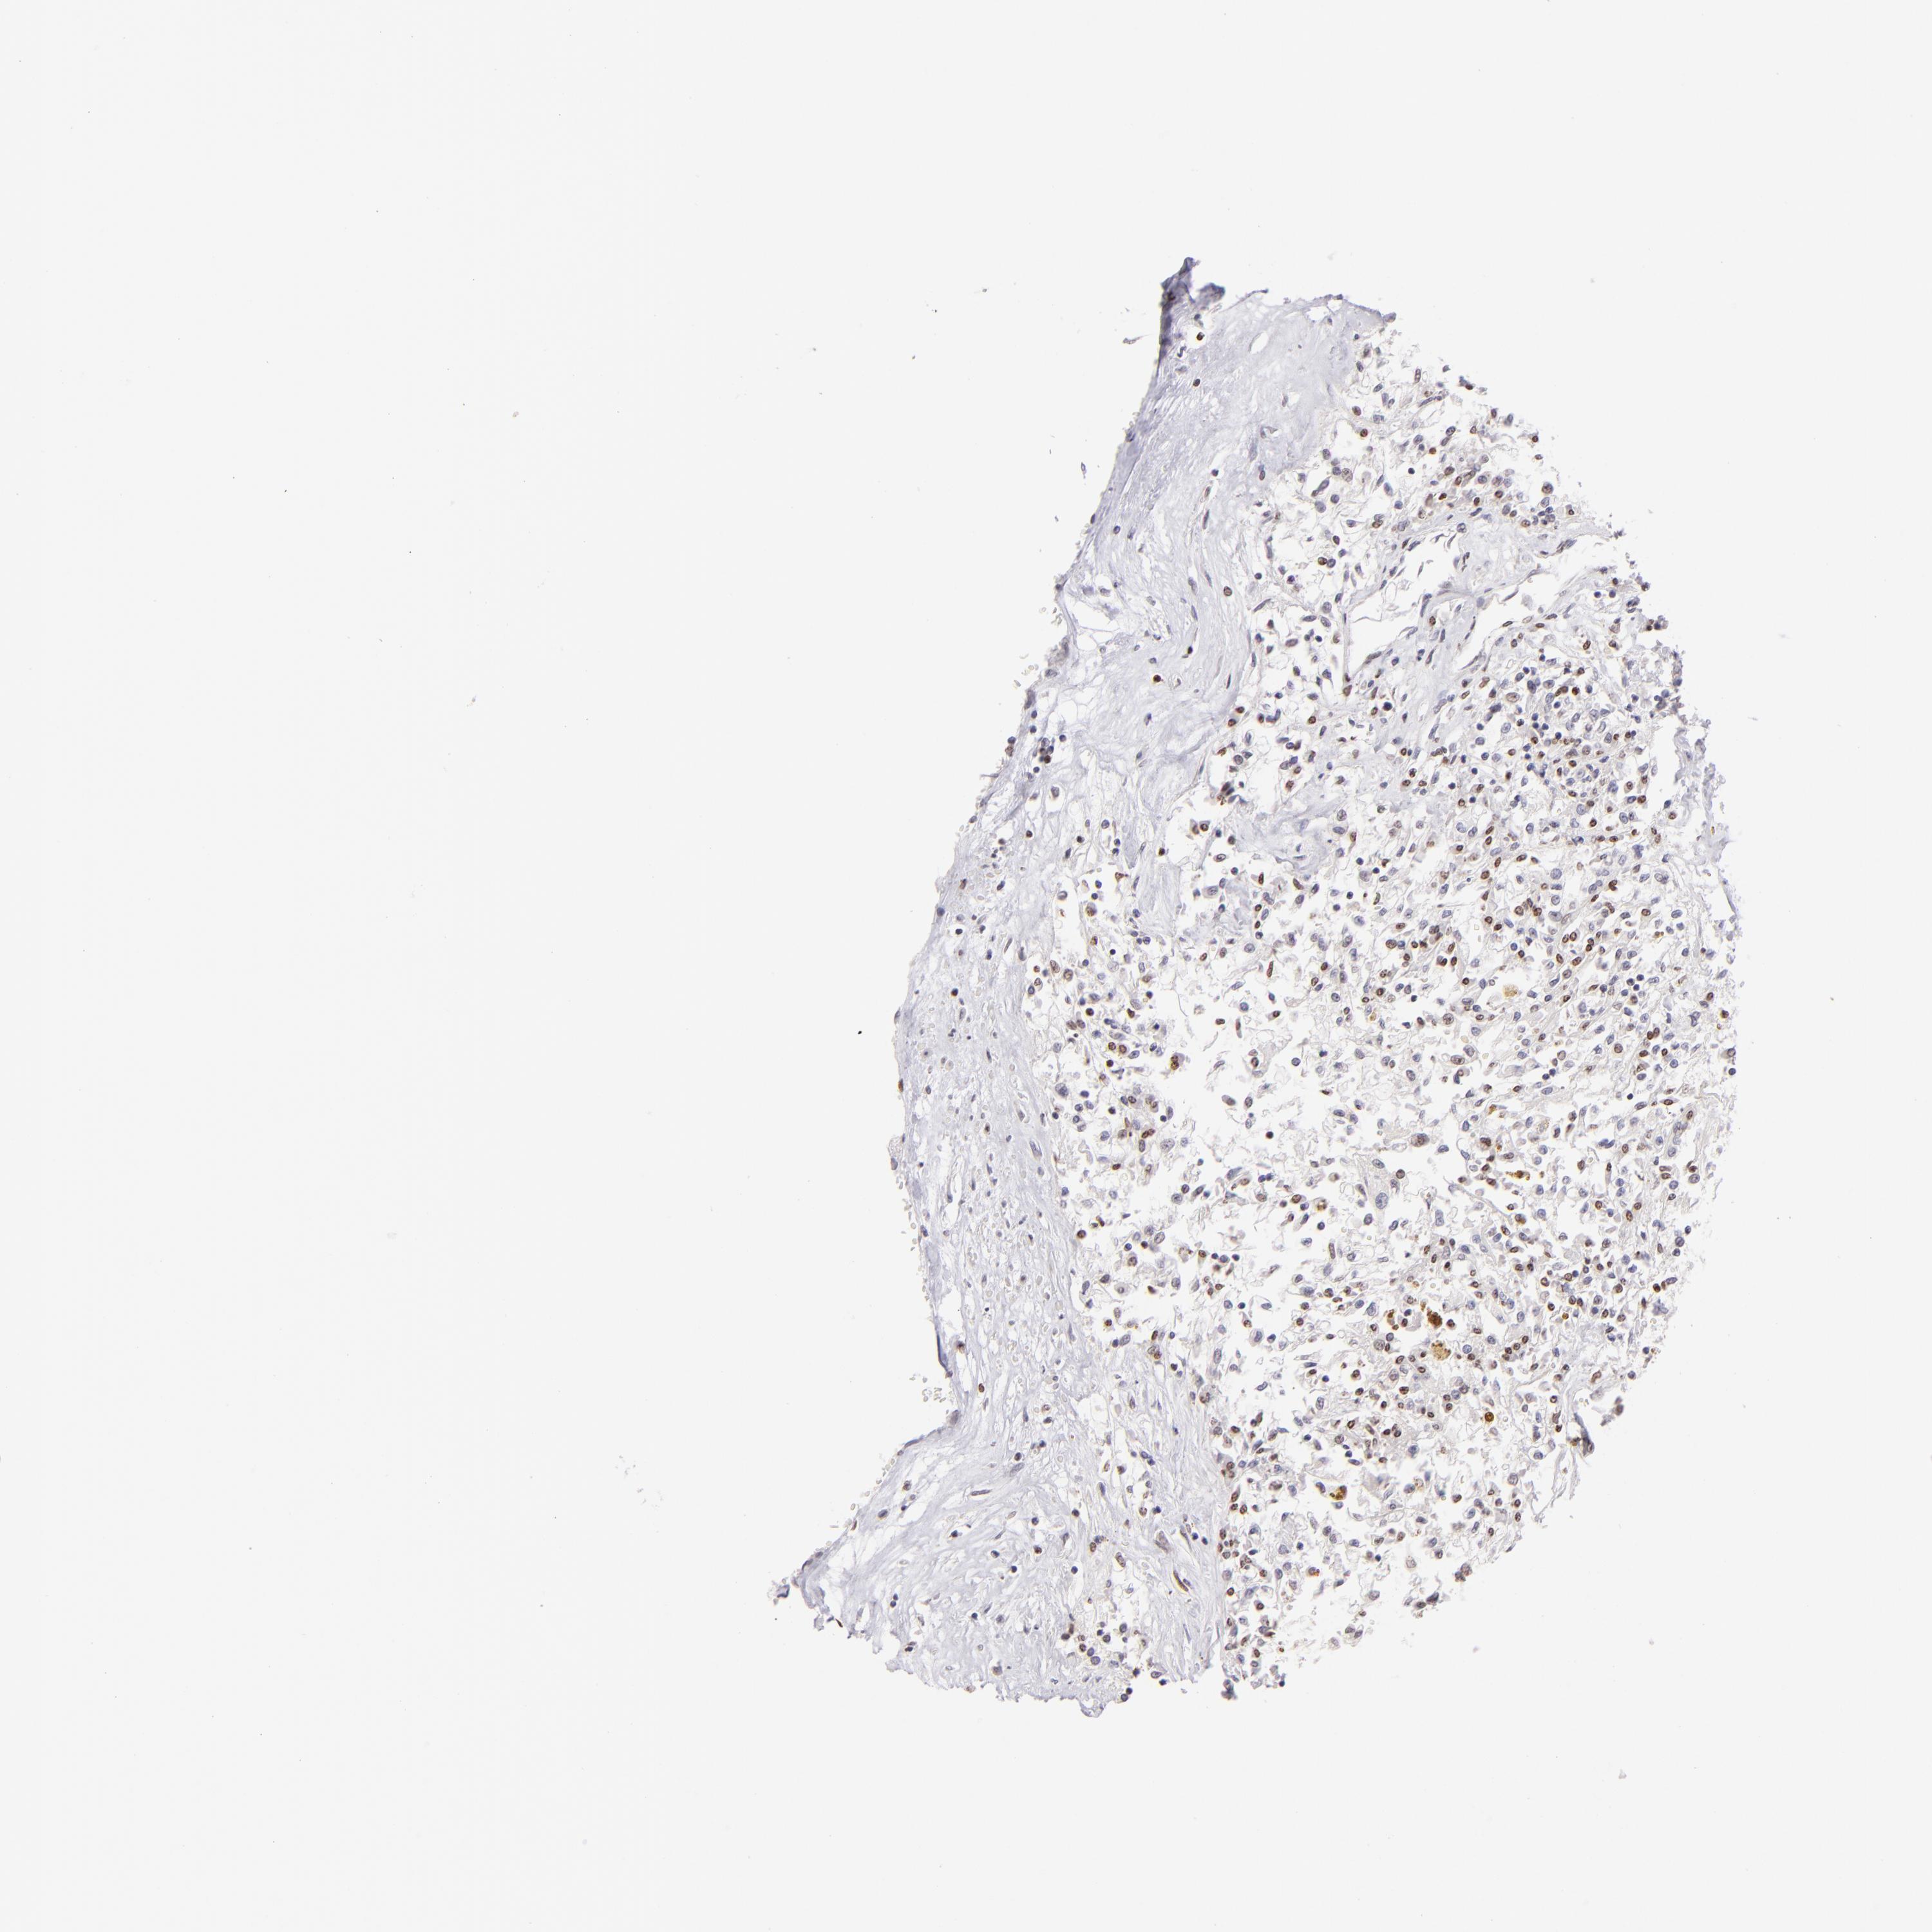

KIDNEY RENAL CLEAR CELL CARCINOMA (VALIDATION) - Interactive survival scatter ploti

The Survival Scatter plot shows the clinical status (i.e. dead or alive) for all individuals in the patient cohort, based on the same data that underlies the corresponding Kaplan-Meier plots. Patients that are alive at last time for follow-up are shown in blue and patients who have died during the study are shown in red.

The x-axis shows the expression levels (FPKM) of the investigated gene in the tumor tissue at the time of diagnosis. The y-axis shows the follow-up time after diagnosis (years). Both axes are complimented with kernel density curves demonstrating the data density over the axes. The top density plot shows the expression levels (FPKM) distribution among dead (red) and alive patients (blue). The right density plot shows the data density of the survived years of dead patients with high and low expression levels respectively, stratified using the cutoff indicated by the vertical dashed line through the Survival Scatter plot. This cutoff is automatically defined based on the FPKM cutoff that minimizes the p-score. The cutoff can be changed by dragging the vertical line or by entering a cutoff value in the square labeled "Current cut-off".

Under the Survival Scatter plot the p-score landscape (black curve; left axis) is shown together with dead median separation (red curve; right axis). Dead median separation is the difference in median mRNA expression between patients who have died with high and low expression, respectively. It is calculated as follows: median FPKM expression of dead patients with high expression - median FPKM expression of dead patients with low expression. This is intended to aid the user in visually exploring custom cutoffs and the associated p-scores and dead median separation.

Individual patient data is displayed and can be filtered by clicking on one or more of the category buttons on the top of the page. Categories describing expression level and patient information include: high, low, alive, dead, female, male and tumor stages. The scale of the x-axis can be toggled between linear and log-scale by clicking on the "x log" button. Mouse-over function shows TCGA ID, patient information and mRNA expression (FPKM) for each patient.

& Survival analysisi

Kaplan-Meier plots summarize results from analysis of correlation between mRNA expression level and patient survival. Patients were divided based on level of expression into one of the two groups "low" (under cut off) or "high" (over cut off). X-axis shows time for survival (years) and y-axis shows the probability of survival, where 1.0 corresponds to 100 percent.

POU2F1 is not prognostic in Kidney Renal Clear Cell Carcinoma (validation)

Best expression cut offi

Based on the FPKM value of each gene, patients were classified into two groups and association between prognosis (survival) and gene expression (FPKM) was examined. The best expression cut-off refers the FPKM value that yields maximal difference with regard to survival between the two groups at the lowest log-rank P-value. Best expression cut-off was selected based on survival analysis .

When clicking on this number, the vertical dashed line indicating cut-off, the interactive survival plot, and the Kaplan-Meier curve will be adjusted to show results based on the best expression cut-off.

: 3.37

Median expressioni

Median expression refers to the median FPKM value calculated based on the gene expression (FPKM) data from all patients in this dataset. When clicking on this number, the vertical dashed line indicating cut-off, the interactive survival plot, and the Kaplan-Meier curve will be adjusted to show results based on the median expression.

: N/A

Median follow up timei

Median follow up time refers to the median time (years) after diagnosis with this type of cancer, based on clinical data from all patients in this dataset.

P scorei

Log-rank P value for Kaplan-Meier plot showing results from analysis of correlation between mRNA expression level and patient survival.

N/A

5-year survival highi

5-year survival for patients with higher expression than the expression cutoff.

For melanoma and glioma, 3-year survival is shown.

5-year survival lowi

5-year survival for patients with lower expression than the expression cutoff.

TCGA RNA samplesi

RNA-seq data is reported as average FPKM (number Fragments Per Kilobase of exon per Million reads), generated by the The Cancer Genome Atlas (TCGA) .

Normal distribution across the dataset is visualized with box plots, shown as median and 25th and 75th percentiles. Points are displayed as outliers if they are above or below 1.5 times the interquartile range. FPKM values of the individual samples are presented next to the box plot.

Average pTPM 3.2

Number of samples 100